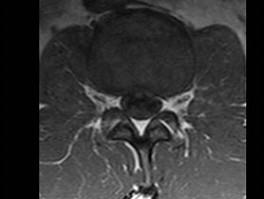

问题 男,45岁,背部隐痛半年余,请结合影像学检查,选出最可能的诊断 ( )

选项 A、椎间盘突出 B、神经根鞘囊肿 C、硬膜外纤维化 D、椎管内肿瘤 E、椎间盘炎

答案 A